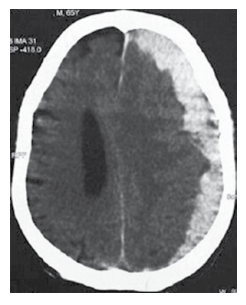

Homem de 72 anos chega ao pronto-socorro com náuseas, vômitos e cefaleia nas últimas 36 horas. O familiar relata quadro de irritação e esquecimento nas últimas duas 2 semanas. Ele leva um estilo de vida ativo, mas sofreu um acidente de bicicleta há 2 semanas. O histórico é notável para angina estável e hipertensão arterial. Ele bebe há 30 anos, quase que diariamente (cerca de 2 copos de uísque). Ao exame físico: ele está desorientado para o tempo, lugar ou pessoa; pressão arterial: 170 x 100 mmHg; reflexos tendinosos profundos: 4+/4 em hemicorpo esquerdo e 2+/4 à direita; Babinski positivo à esquerda. A tomografia sem contraste é mostrada a seguir